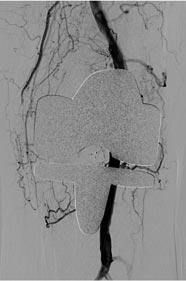

Bij lichamelijk onderzoek wordt een vitale man gezien. Rechts in de onderbuik is in staande positie een zwelling voelbaar die terug te duwen is. Om de aard van deze zwelling verder te duiden, wordt een echo verricht waarop een hernia Spigelii te zien is (zie figuur 1 en 2). Opvallend genoeg lijkt de breukzak zelfs inhoud te bevatten, mogelijk de appendix vermiformis. Een aanvullende CT-scan bevestigt dit beeld (zie figuur 3). Er is geen teken van appendicitis, maar er is wel geïnfiltreerd vetweefsel in de ileocoecaalhoek met een nodulair verdikte lymfeklier.

Achtergrond